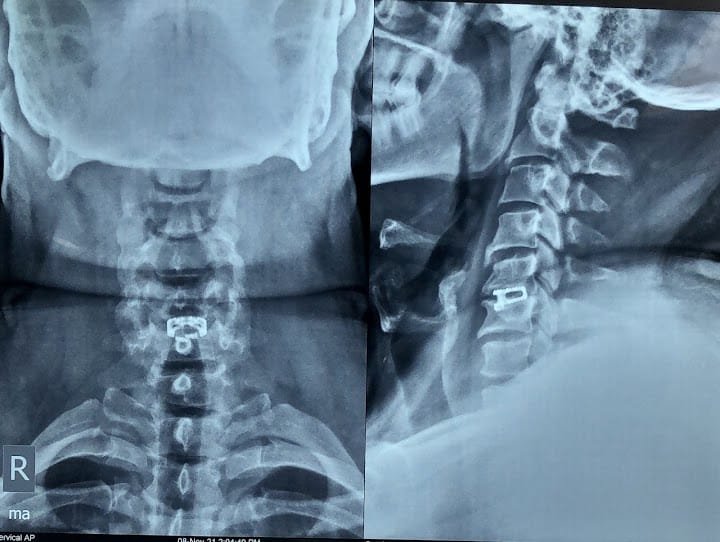

Spine Surgery

Dr. Rahul is a highly experienced spine surgeon specializing in diagnosing and treating spinal conditions. He performs a wide range of surgical options for spinal conditions, including minimally invasive techniques, spinal fusion, and disc replacement.

Neck Pain

Neck pain can be caused by a variety of factors, including poor posture, muscle strain, and degenerative conditions such as arthritis. Dr. Rahul provides specialized services in the diagnosis and treatment of neck pain.